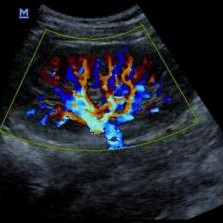

Ecografia / Ultrassonografia